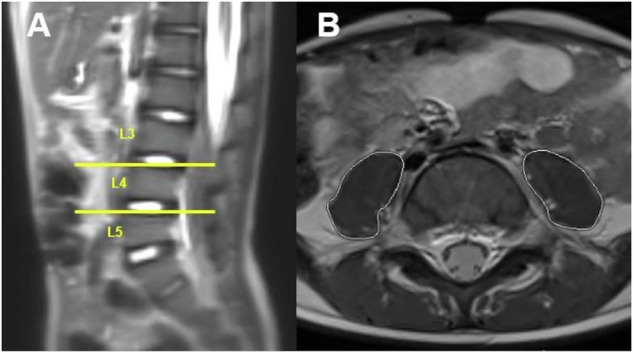

Methods: A retrospective analysis of MRI examinations was conducted on 29 children and adolescents with CNO. CNO lesions were segmented. Sarcopenia was assessed using the total psoas muscle index (PMI) at lumbar vertebral levels L3/4 and L4/5. Measurements were taken at four time points during the disease course (T1: baseline, T2-T4: follow-up). Based on the PMI, patients were classified as sarcopenic or non-sarcopenic, and the progression of CNO lesions and the impact of sarcopenia were analyzed.